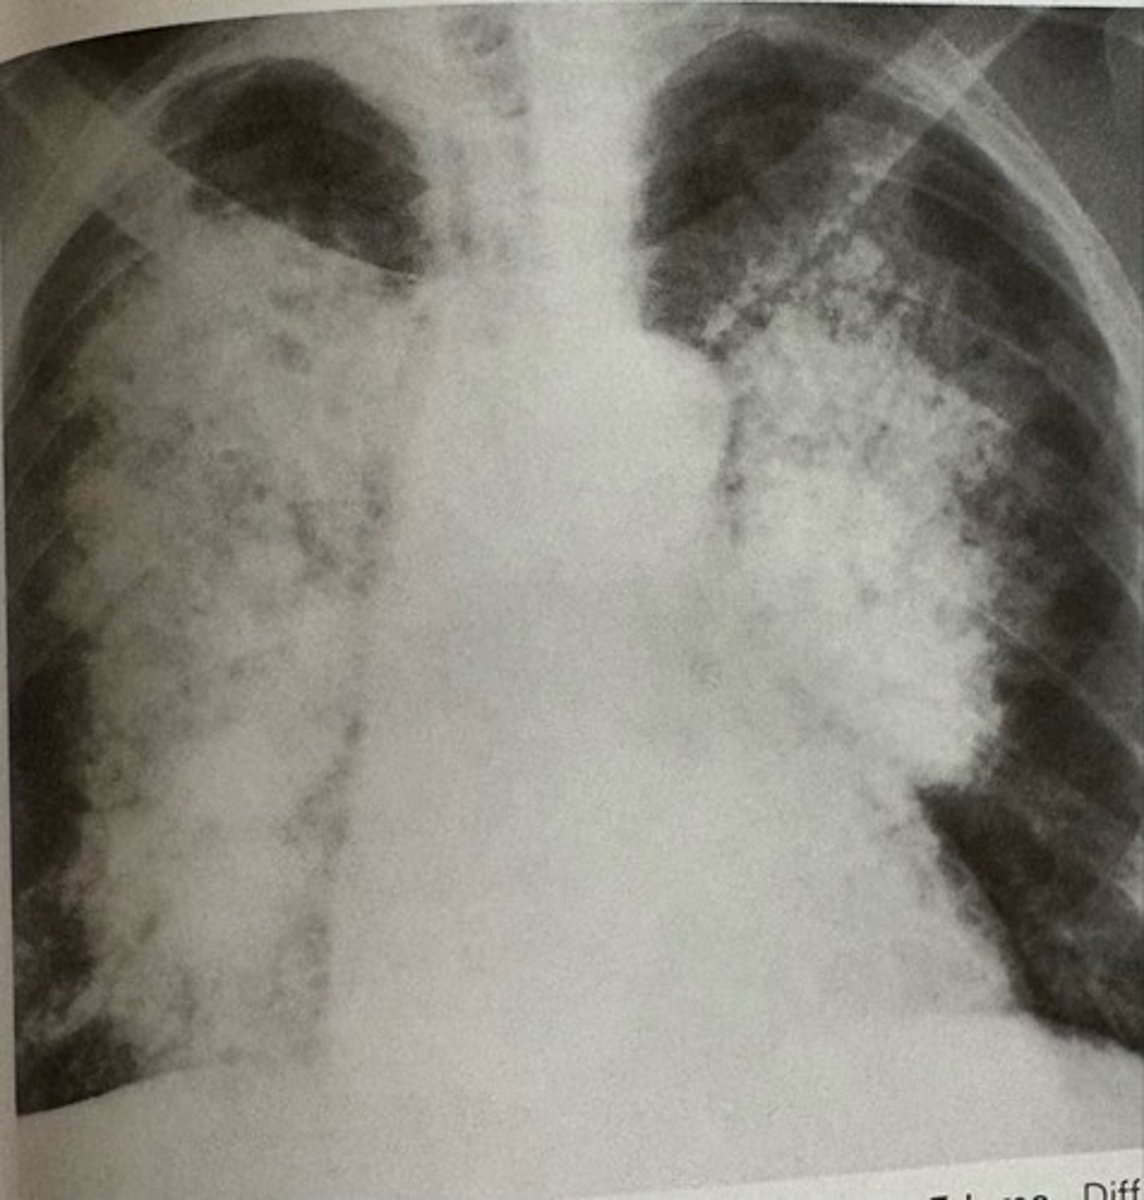

butterfly pattern of severe pulmonary edema

what pathology is present?